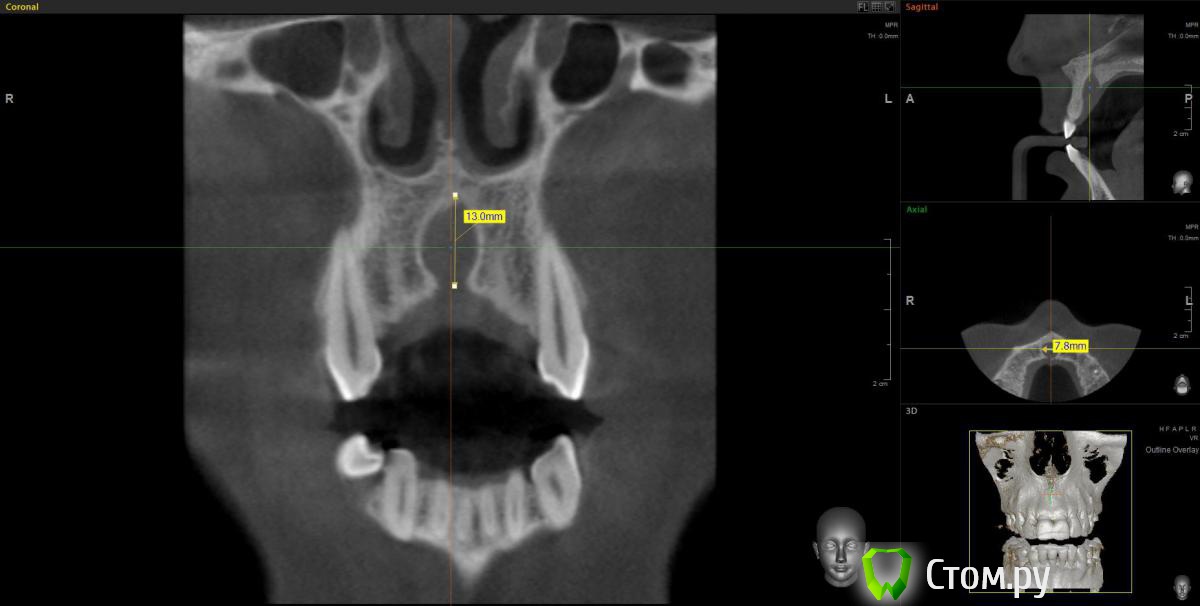

kriokov Опубликовано 20 марта, 2012 Поделиться Опубликовано 20 марта, 2012 Пац 60 лет, 13.03- диагносцирована нагноившаяся киста в\челюсти, вскрыт гнойник, антибактериальная и симптоматическая терапия. На КТ киста до 4 куб см ориентировочно, сквозной дефект с вестибулярной на небную поверхность, деструкция носонебного канала, деструктивный очаг небно за корнем 11. дно носа не критично. Имплантация в перспективе не планируется.Через 1 месяц планируется штатная цистэктомия с удалением 21 и 22. Коллеги, кто как небно мебрану выставляет? Дефект кости на небе 10 на 10 мм. Сам думаю, что под полнослойный лоскут на небе придется устанавливать, попробую отслоиться со стороны костной раны. Ссылка на комментарий

wladdX Опубликовано 22 января, 2014 Поделиться Опубликовано 22 января, 2014 (изменено) Пациентка 33-х лет, обратилась с жалобами на болезненную припухлость на тв. нёбе. При обследовании выявлена киста резцового канала, самопроизвольно вскрывшаяся.Через перф.отверстие отмыта, воспаление стихло, свищевого хода не сформировалось (перф.отверстие эпителизировалось). Встаёт вопрос об операции. Планируется нёбный доступ. Как думаете, коллеги? Изменено 22 января, 2014 пользователем wladdX Ссылка на комментарий